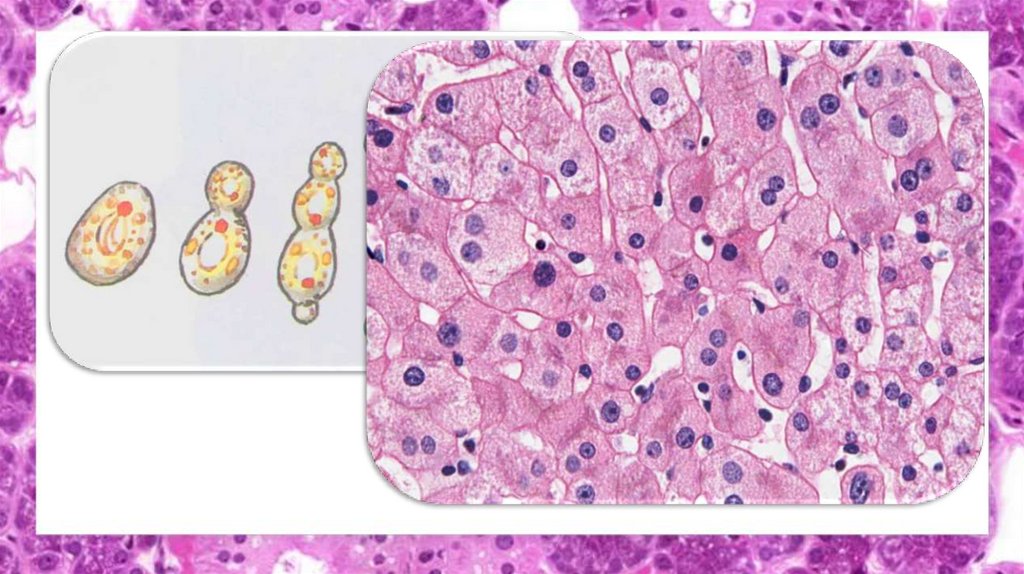

Клеточный цикл:

1.

Интерфаза (23,5 ч):

- Постмитотический

(пресинтетический) G1 (9 ч)

-

Синтетический S (10 ч)

- Премитотический

(постсинтетический) G2 (4,5 ч)

2. Митоз (0,5 ч):

Профаза

Метафаза

Анафаза

Телофаза